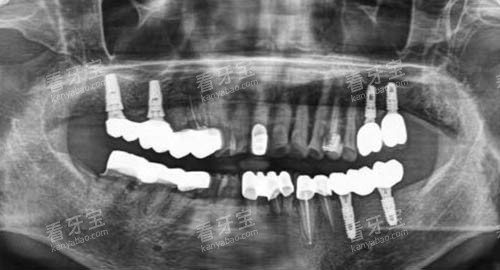

在种植牙方面,医生们熟练掌握各种较高的种植技术,能够根据患者的口腔情况和需求,选择合适的种植体和种植方案。

例如,对于一些牙槽骨条件较差的患者,医生会采用骨增量技术,为种植体提供更好的支撑。

例如,对于种植牙患者,医生会考虑患者的年龄、身体状况、经济条件等因素,选择合适的种植体和种植方案。

在种植牙方面,许多患者因为牙齿缺失而影响了咀嚼功能和美观。

通过泉州丰泽维乐口腔的种植牙治疗,他们重新拥有了健康的牙齿。

例如,一位60多岁的老先生,由于多年的牙齿缺失,导致咀嚼困难,身体也越来越差。

在该机构接受种植牙治疗后,老先生的咀嚼功能得到了明显改善,身体状况也逐渐好转。